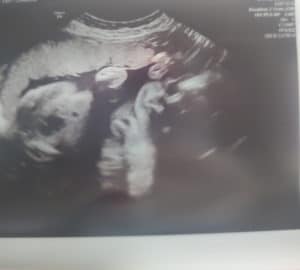

Now we can’t wait to meet our little girl Cheyenne! She is at 1bl 14oz I’m 26 weeks and 2 days she’s very healthy and doing good at the doctor said!